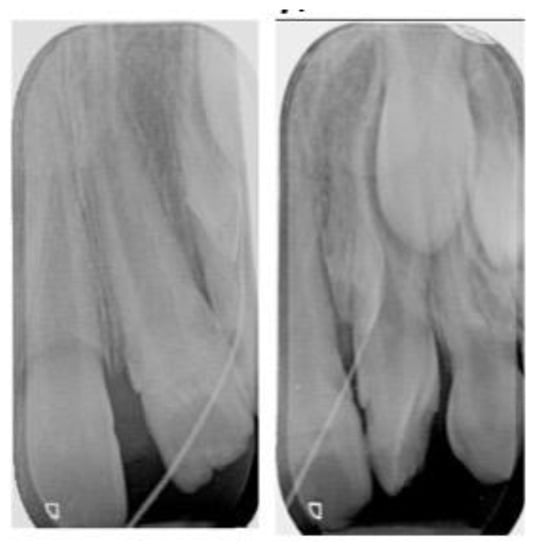

2.2. Treatment Plan and Progress